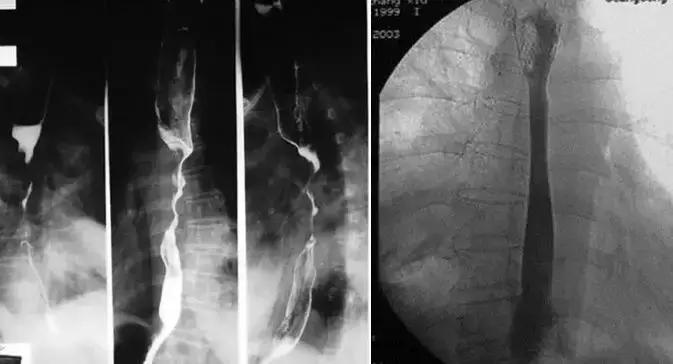

1、食道支架技术

2、胆道支架技术